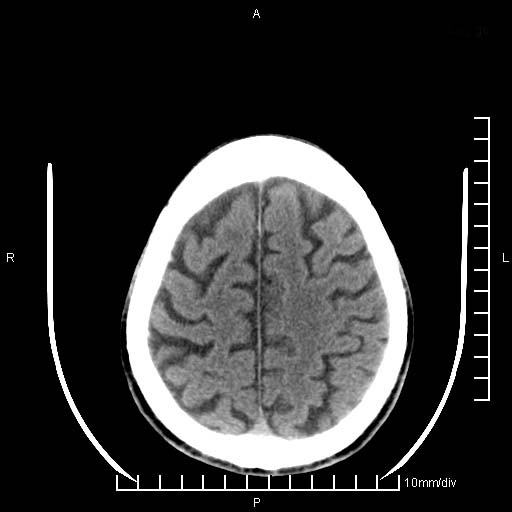

临床以双下肢浮肿,疼痛收治,无明显神经系统症状,既往无梗塞,出血病史。左颞叶见低密度灶,考虑什么?

考虑左侧颞叶脑软化灶。

无强化 无占位 软化灶吧

无强化、 无占位、局部脑沟增宽, 软化灶吧。